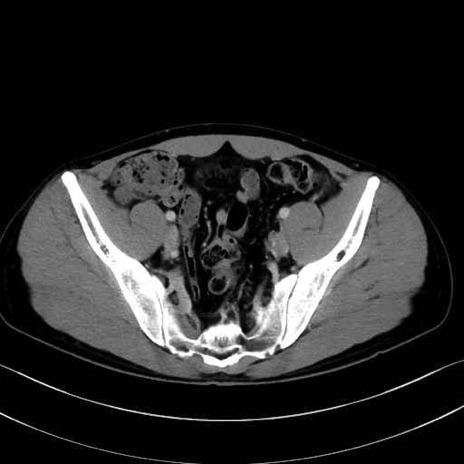

内閉鎖筋(obturator internus) のCT画像の解剖

2. 腸腰筋群と骨盤底筋

大腰筋 (Psoas major)

腸骨筋 (Iliacus)

内閉鎖筋 (Obturator internus)